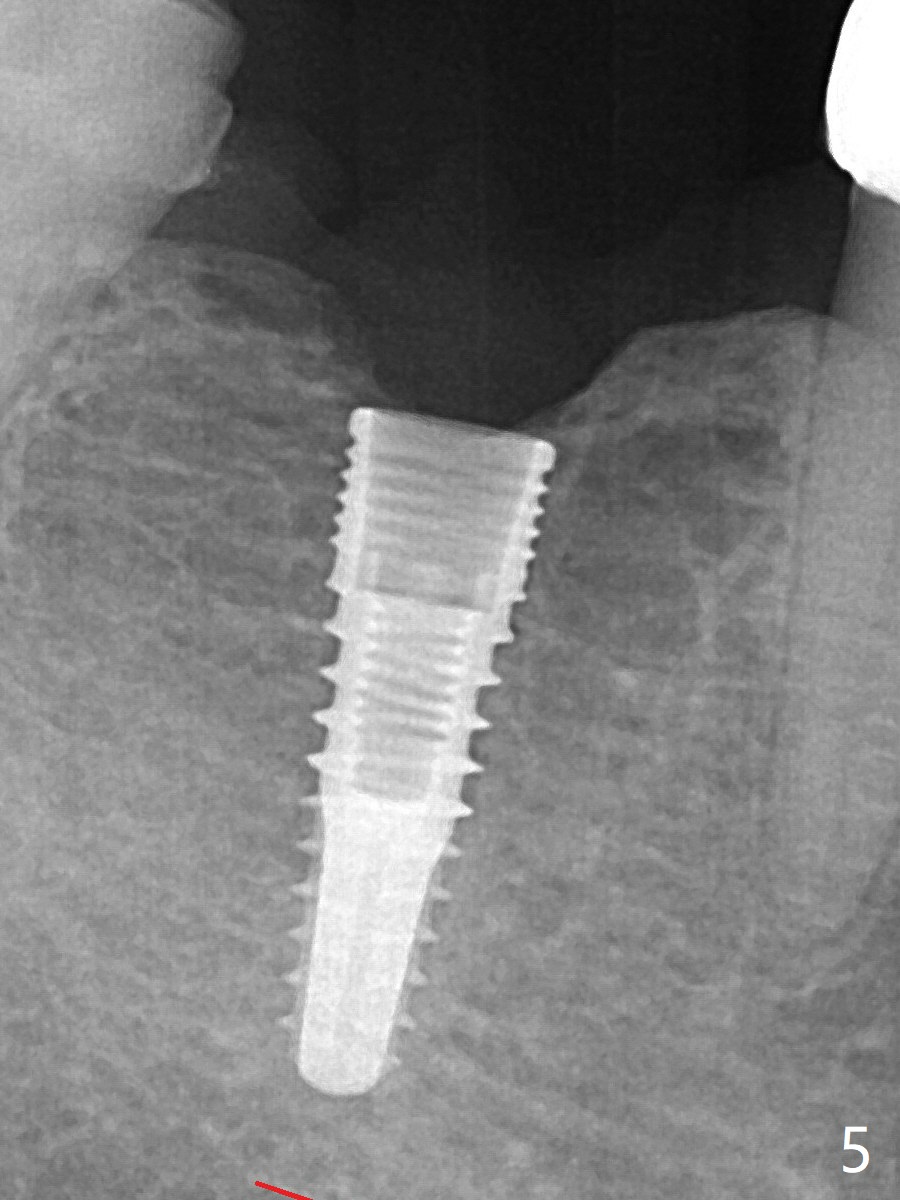

When a 3.8x12 mm SM implant is placed with 40 Ncm, there is 1-2 mm cortical bone buccolingually (primary stability, Fig.4,5).  The thick cortices do not seem to be easy to be bent, i.e., expanded.